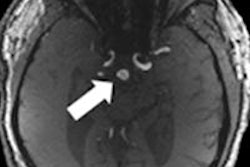

Dedicated 7-tesla MRI of the female pelvis shows the feasibility and potential of in vivo, ultrahigh-field pelvic imaging, which could help clinicians more accurately diagnose pelvic parenchymatous and vasculature disease, according to a study from Germany.Dr. Thomas Lauenstein, from Essen University Hospital, and colleagues included 14 healthy women in the study, using a custom-built eight-channel MRI radiofrequency body coil. The exam protocol included T1-weighted fat-saturated 2D fast low-angle shot (FLASH), T1-weighted fat-saturated 3D FLASH, and T2-weighted turbo spin echo.

Two radiologists assessed each exam's visualization of pelvic anatomy, vasculature, tissue contrast, and overall image quality, using a five-point scale (with a score of 1 equal to nondiagnostic visualization and a score of 5 meaning excellent visualization).

For the T1-weighted sequences, 2D FLASH imaging had higher scores for all assessed structures than 3D FLASH MRI, with overall image quality receiving the highest scores. T2-weighted turbo-spin echo imaging produced a moderate to high visualization of the anatomy of the uterus.

Seven-tesla MRI is a feasible way to visualize the female pelvis in finer detail, the team concluded.